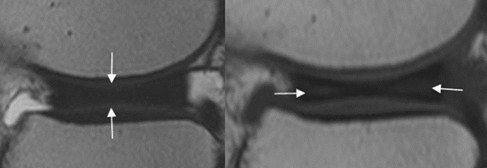

La risonanza magnetica (RM) rappresenta il gold-standard per la conferma diagnostica e per la pianificazione preoperatoria, in quanto consente di caratterizzare accuratamente la morfologia e la stabilità del menisco, identificare le eventuali lesioni associate concomitanti (Fig 3).